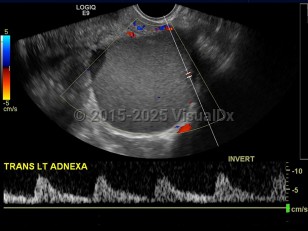

The endometrium is the innermost lining layer of the uterus. Its function is to stabilize and support an early pregnancy. When fragments of endometrial lining are found outside of the uterine cavity, this is referred to as endometriosis.

The exact etiology of this condition is unclear, but the prevailing thoughts are toward retrograde menstruation (endometrial fragments pushed into the abdomen through the fallopian tubes) and localized lymphatic spread. Areas affected can include all abdominal organs but most commonly involve the ovaries, bladder, fallopian tubes, and the uterine support ligaments. Less common sites of involvement may include the umbilicus, incisional scars, and the omentum.